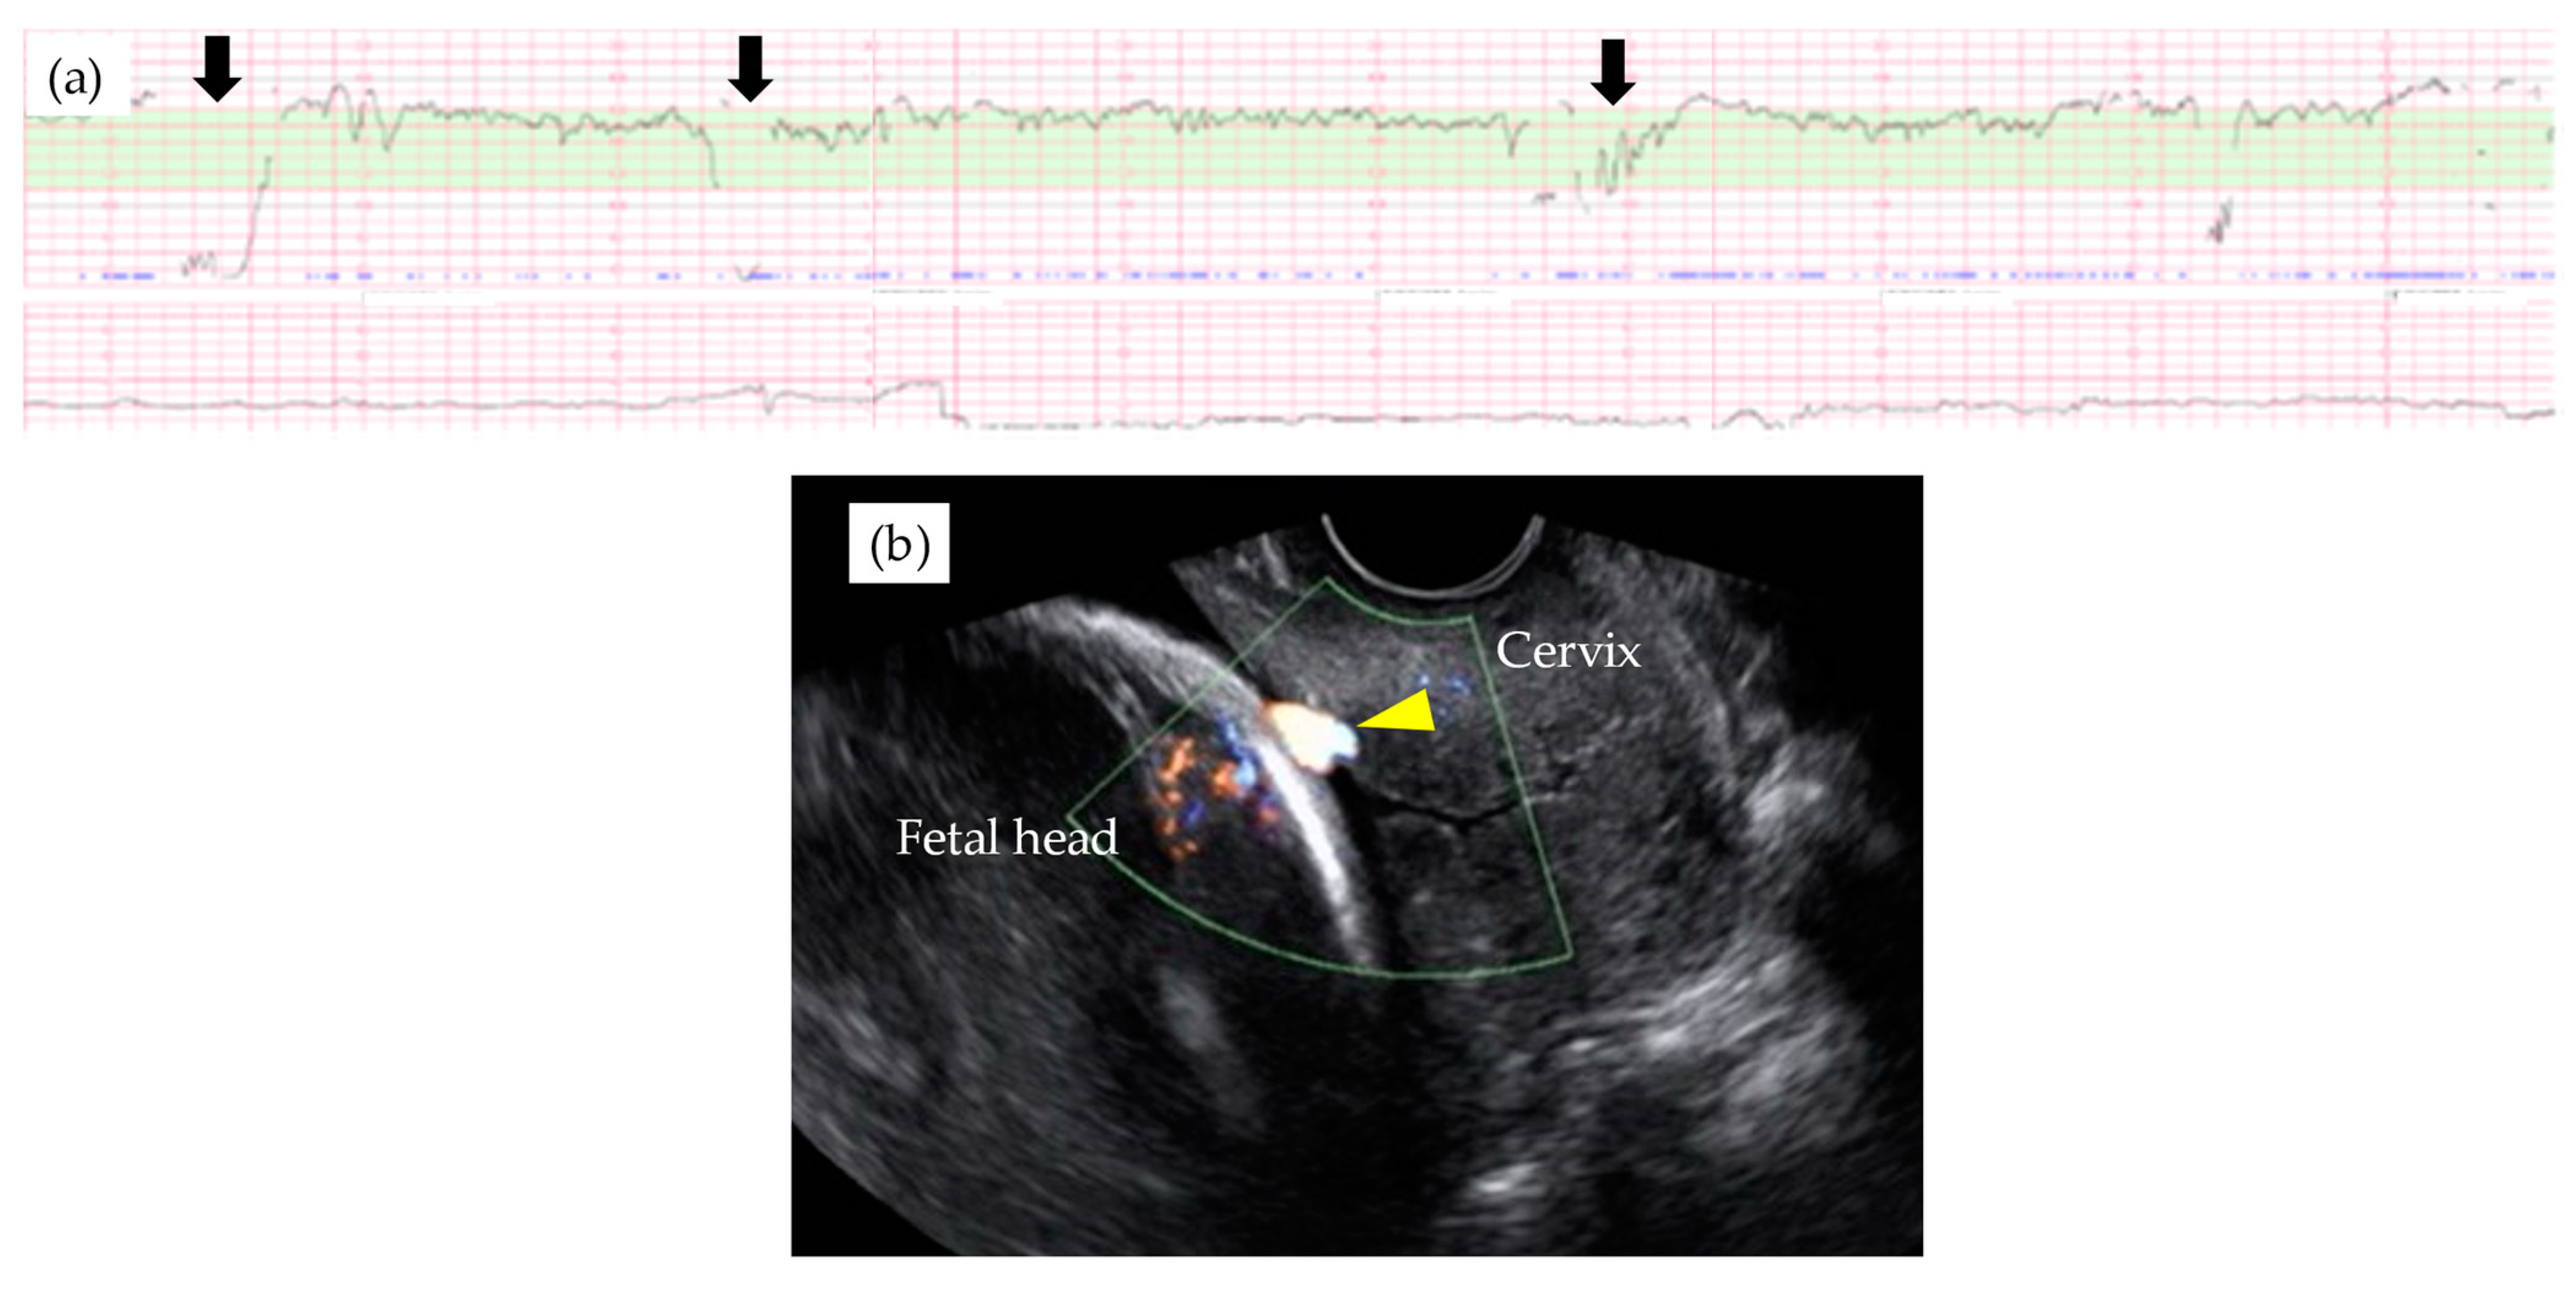

Table 3 shows the results of management and operative outcomes. In 31 cases (56.4%), including three twin pregnancies, tocolytic therapy was necessary (ritodrine hydrochloride and/or magnesium sulfate), and a steroid for fetal lung maturation was given in 9/13 cases (69.2%) delivered before the 34th GW. An abnormal fetal heart rate pattern without uterine contractions was detected in one case in the type 1 group, and this case exhibited a relatively thick artery near the internal ostium (Figure 2). Cervical cerclage via the McDonald technique was performed in two cases in the type 1 group. One of these cases was a singleton pregnancy at 20th GW and a cervical length of 2.1 cm, delivered by CS at 33rd GW. The other was a monochorionic-diamniotic pregnancy case at 20th GW and a cervical length of 1.7 cm, delivered by CS at 31st GW; this patient had a previous history of preterm singleton delivery at 34th GW. Blood flow of fetal vessels was confirmed post-cerclage in both cases (Figure 3). Resolution was observed in 12 cases (21.8%) in total. An emergent CS was performed in 25 cases with increased uterine contractions and in one case with an indication of hypertensive disorder of pregnancy; none of these cases experienced the premature rupture of membranes. Although the Ward technique was more frequently used in the non-type 1 group, the details as to operative outcome showed no significant difference between the two groups. The transection of the placenta to approach the fetus was not used in any of the cases. All cases underwent a cesarean section, even in those cases of resolution of VP.

Figure 2. Abnormal fetal heart rate patterns (a) in a type 1 VP case with relatively large arterial vasa previa at 29th GW (b). Note that fetal heart rate decelerations were observed without uterine contraction (black arrown in Figure 2a) and relatively thick velamentous vessel was identified by the trans-vaginal ultrasound scan (yellow arrow head in Figure 2b).